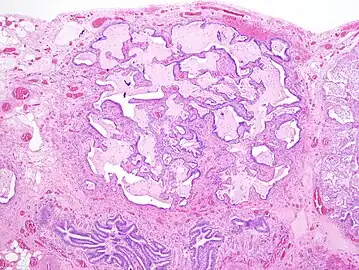

The histologic hallmarks of UIP, as seen in lung tissue under a microscope by a pathologist, are interstitial fibrosis in a "patchwork pattern", honeycomb change and fibroblast foci (see images below).[6] [7]

Appearance of usual interstitial pneumonia (UIP) in a surgical lung biopsy at low magnification. The tissue is stained with hematoxylin (purple dye) and eosin (pink dye) to make it visible. The pink areas in this picture represent lung fibrosis (collagen stains pink). Note the "patchwork" (quilt-like) pattern of the fibrosis.